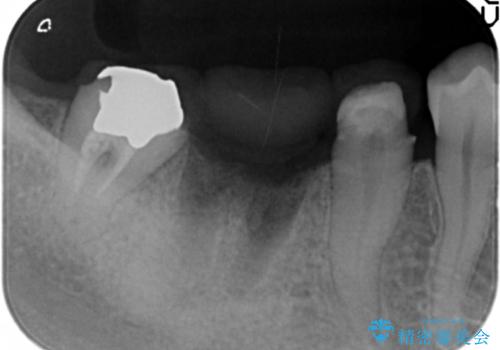

銀歯の下に大きな虫歯の再発

- 銀歯が脱離し、再装着を求めて来院されました。

脱離した歯を精査したところ、大きな虫歯の再発・穿孔箇所が複数認められ長期的な予後を見込むことが難しかったため抜去が妥当であると診断しました。